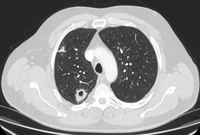

Cortes de tomografia computadorizada (TC) com exemplos de nódulos solitários semissólidos

Do acervo de Dr. George Tsaknis, MD, PhD, FRCP (Londres), MRQA, MAcadMEd, PGCert; usado com permissão